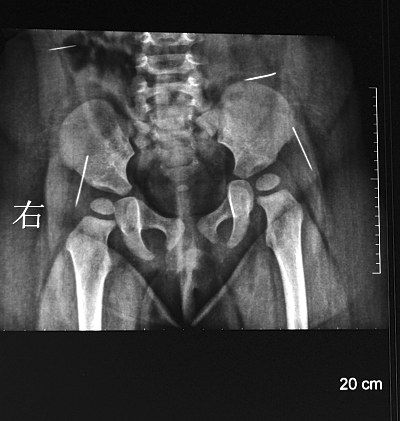

萌萌手術(shù)前拍攝的CT片顯示,4個(gè)白亮的針狀物分布在腰部和臀部?jī)蓚?cè)。據(jù)主刀醫(yī)生、淮安市婦幼保健院小兒科副主任陳衛(wèi)兵介紹,4根縫衣針長(zhǎng)度從1.5厘米到約2厘米不等,都沒(méi)有針鼻兒。臀部的兩根針有可能觸及坐骨神經(jīng),腰部的那根眼看就要移動(dòng)到肝臟位置。

陳衛(wèi)兵介紹,手術(shù)難度很大,為準(zhǔn)確定位萌萌體內(nèi)的4根針,他邊看X光片,邊電話聯(lián)系放射科主任,參照早晨剛拍的CT片來(lái)定位。取出4根針后,他發(fā)現(xiàn)最后取出的那根比X片上顯示的短了半截,隨后他又將斷針找了出來(lái)。